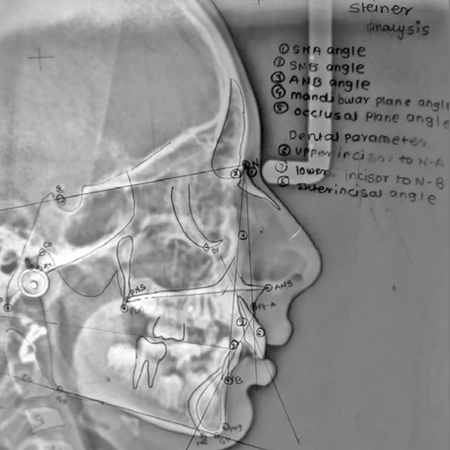

Precisão da identificação de pontos cefalométricos usando softwares baseados em inteligência artificial: um estudo comparativo

Introdução: A cefalometria tem sido, por muito tempo, um pilar do diagnóstico e do planejamento do tratamento ortodôntico. Embora tradicionalmente realizada de forma manual, a análise cefalométrica tem migrado cada vez mais para so...

Accuracy of cephalometric landmark identification on artificial intelligence-based software: a comparative study

Introduction: Cephalometry has long been a cornerstone of orthodontic diagnosis and treatment planning. While traditionally performed manually, cephalometric analysis has increasingly shifted toward semi-automated or fully automated comp...

Validação de um aplicativo baseado em IA (WebCeph) para análise cefalométrica em pacientes pediátricos: avaliação de confiabilidade, reprodutibilidade e rapidez

Introdução: Embora os aplicativos de análise cefalométrica baseada em IA sejam amplamente utilizados, a maioria dos estudos de validação usou radiografias de adultos. Os pontos cefalométricos apresentam maior variabilidade em cria...

Pediatric validation of an AI-assisted smartphone application (WebCeph) for cephalometric analysis: reliability, reproducibility and time-efficiency assessment

Introduction: Although AI-assisted cephalometric applications are widely used, most validation studies involve adult radiographs. Pediatric craniofacial landmarks show greater variability due to growth, which may influence automated land...